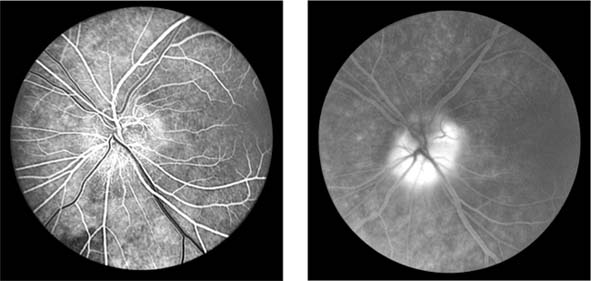

In anterior segment ischemia, patients develop iritis, intraocular pressure changes, and pupillary abnormalities. In retinal ischemia (Figure 15-12A), patients show evidence of capillary dilation and hemorrhages, capillary occlusion, new vessels at the optic disk, and cotton-wool spots.

Figure 15-12

Figure 15-12: A: Fluorescein angiogram of left fundus in a patient with chronic ocular ischemia secondary to Takayasu's disease. Note capillary dilation, leakage of dye, retinal hemorrhages, cotton-wool spots, and neovascularization of the optic nerve head. B: Fluorescein angiogram, showing leakage at optic disk and macula in a patient with chronic ocular ischemia secondary to dural arteriovenous fistula.

Carotid Cavernous Fistula